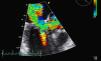

Foi internada para compensação de sua insuficiência cardíaca. O ecocardiograma transtorácico (ECOTT) realizado no primeiro dia de internamento (FC entre 120-150 bpm) (Figura 1) revelou uma válvula aórtica (VAo) fibrosada mas sem limitação da abertura, com insuficiência ligeira.

A Válvula mitral (VM) encontrava-se fibrocalcificada e com hiperecogenicidade do anel; o folheto anterior e o aparelho subvalvular condicionavam obstrução ao tracto de saída do ventrículo esquerdo (VE), originando gradiente intraventricular de 110mmHg com presença de insuficiência moderada e paroxística (em relação provável com a intermitência da gravidade da obstrução do tracto de saída do VE). Aurícula esquerda gravemente dilatada (6,1cm). O VE encontrava-se hipertrofiado com diâmetro diastólico de 4,3cm e com boa função sistólica global. As cavidades direitas possuíam dimensões normais com pressão arterial pulmonar estimada em 40mmHg.